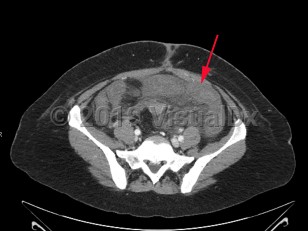

Acute mesenteric ischemia is a sudden interruption or severe reduction in blood flow to the bowel leading to ischemia, necrosis, and ultimately perforation. It is a medical emergency requiring emergent intervention to restore perfusion, often requiring a multidisciplinary approach. Mesenteric ischemia can result from several distinct pathologic entities including embolic disease, arterial thrombosis, mesenteric vein thrombosis, and lack of perfusion due to low flow states or nonocclusive mesenteric ischemia (NOMI).

Patient presentation is characterized by the sudden onset of severe abdominal pain with a benign abdominal examination, often referred to as "pain out of proportion to exam." Many patients will develop vomiting and diarrhea. Bloody diarrhea due to bowel necrosis is a late finding. In occlusive disease, symptoms progress rapidly over hours to days. Those with thrombotic disease may report weeks to months of preceding symptoms suggestive of chronic mesenteric ischemia. These can include abdominal pain worsened after eating (so-called "intestinal angina"), fear of eating, and weight loss. Nonocclusive mesenteric ischemia is often observed in the setting of critical illness. Worsening acidosis, hemodynamic instability, feeding intolerance, diarrhea, and abdominal distention are all worrisome signs.